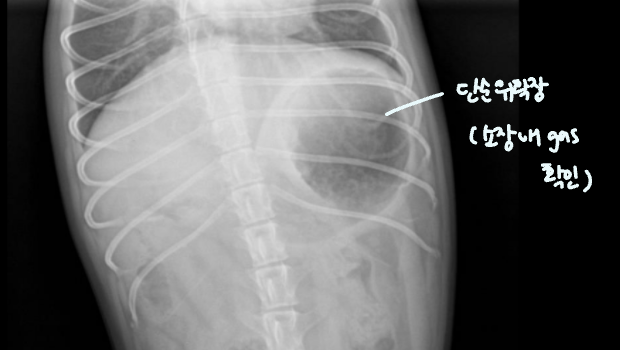

์ํ์ฅ : GD vs. GDV

- GD๋ ์๊ฐ ํ์ฅ๋์ด ์์ผ๋, ์์น๋ ๊ทธ๋๋ก.

- pylorus๊ฐ ํ์๋๋ฉด, ์๋ฐฐ์ถ ๋ถ๋ฅ + ์์ฅ ๋ด gas๊ฐ ์ฐธ.